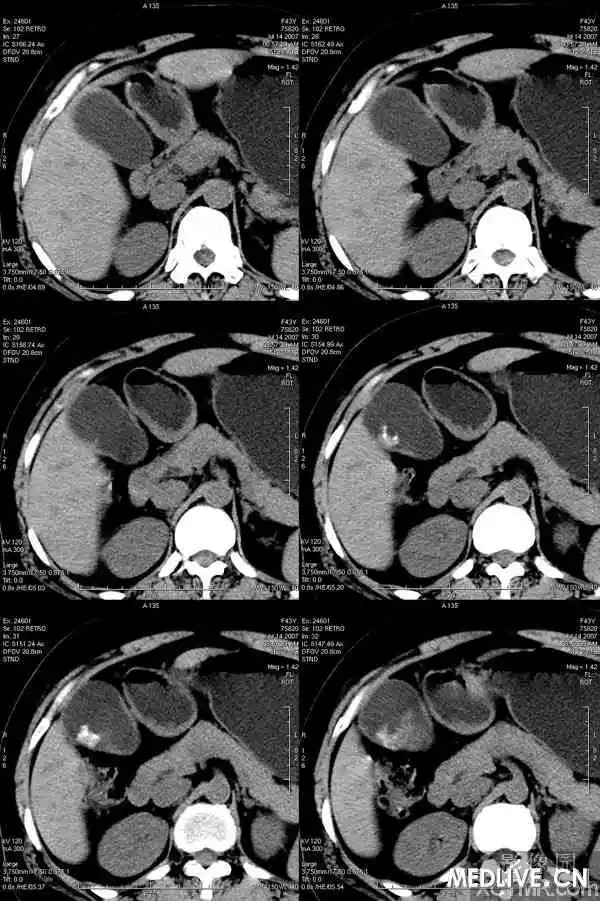

【影像表现】

胆囊内混杂高密度影,内有不规则形钙化,胆囊壁略增厚。

CT表现因结石化学成分不同,可为高密度、等密度、低密度、环状结石。等、低密度结石CT不易发现,胆影葡胺增强检查见胆囊内可移动的充盈缺损可明确。